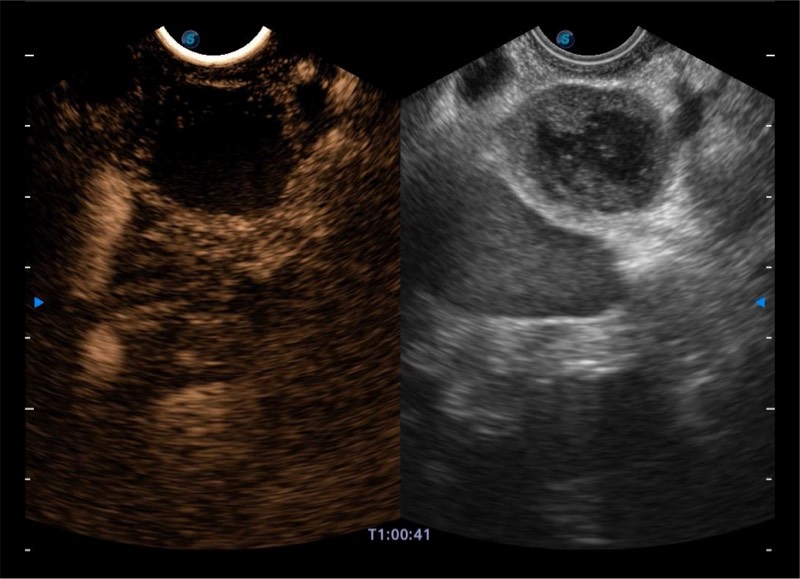

基于二十年的超声技术积累,乐玩lewin国际提供了最新一代的独立超声主机,在提供高质量图像的同时满足多学科使用。具备常见多普勒技术并提供弹性成像、声学造影等高端影像技术。新一代传感器具有更强的抗干扰能力并减少图像伪影。

150°超声扫描角度

4-12MHZ宽频输出